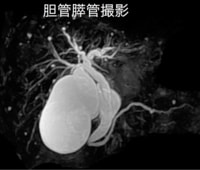

<放射線部の特徴と検査内容>

平成25年より新しく稼働したCT、MRIを始め、マンモグラフィー、骨密度測定、レントゲン画像装置などにより病気の早期発見、早期診断を目指しています。

軟部組織のコントラストに優れ、様々なコントラストパラメーターを有するMRIは、頭頚部、体幹部、脊椎・脊髄、整形領域、心臓領域とほぼ全身に渡る断層画像をあらゆる角度で撮像できます。

MRIの画像